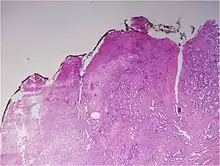

Gleason score 6 (3+3)

Gleason 3

Gleason 3 is a clearly infiltrative neoplasm, with extension into adjacent healthy prostate tissue. The glands alternate in size and shape, and are often long/angular. They are usually small/micro-glandular in comparison to Gleason 1 or 2 grades. However, some may be medium to large in size. The small glands of Gleason 3, in comparison to the small and poorly defined glands of pattern 4, are distinct glandular units. Mentally you could draw a circle around each of the glandular units in Gleason 3.[4][7]